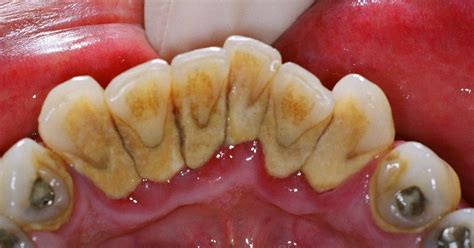

¿Qué es el Sarro Dental?

El sarro, también llamado cálculo dental, es la mineralización de la placa bacteriana que se acumula sobre los dientes. Es decir, cuando la placa no se elimina correctamente mediante la higiene diaria, acaba endureciéndose por la acción de la saliva y los minerales, formando una capa sólida adherida al esmalte.

Imagen de Wikimedia Commons, autor: Shaimaa Abdellatif

A diferencia de la placa, que es blanda y transparente, el sarro es duro, rugoso y puede presentar una coloración amarilla, marrón o incluso negra. Una vez formado, no puede eliminarse con el cepillado: necesita ser retirado por un profesional mediante una limpieza dental.